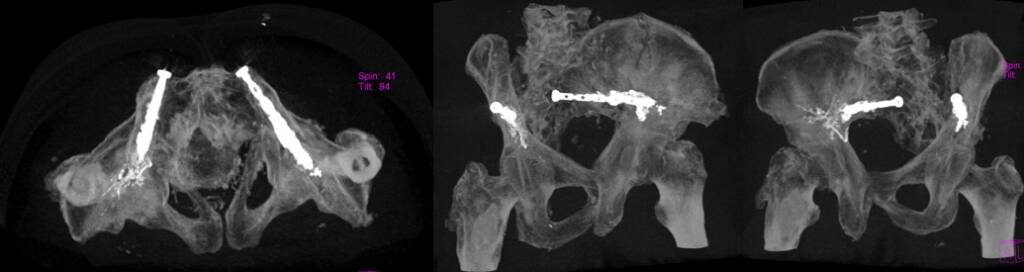

Bone metastases in load-bearing regions (pelvis, femur, humerus)

Percutaneous osteosynthesis is often combined with:

Cementoplasty

Structural stabilization

- Functional preservation

- Reduced need for open surgery